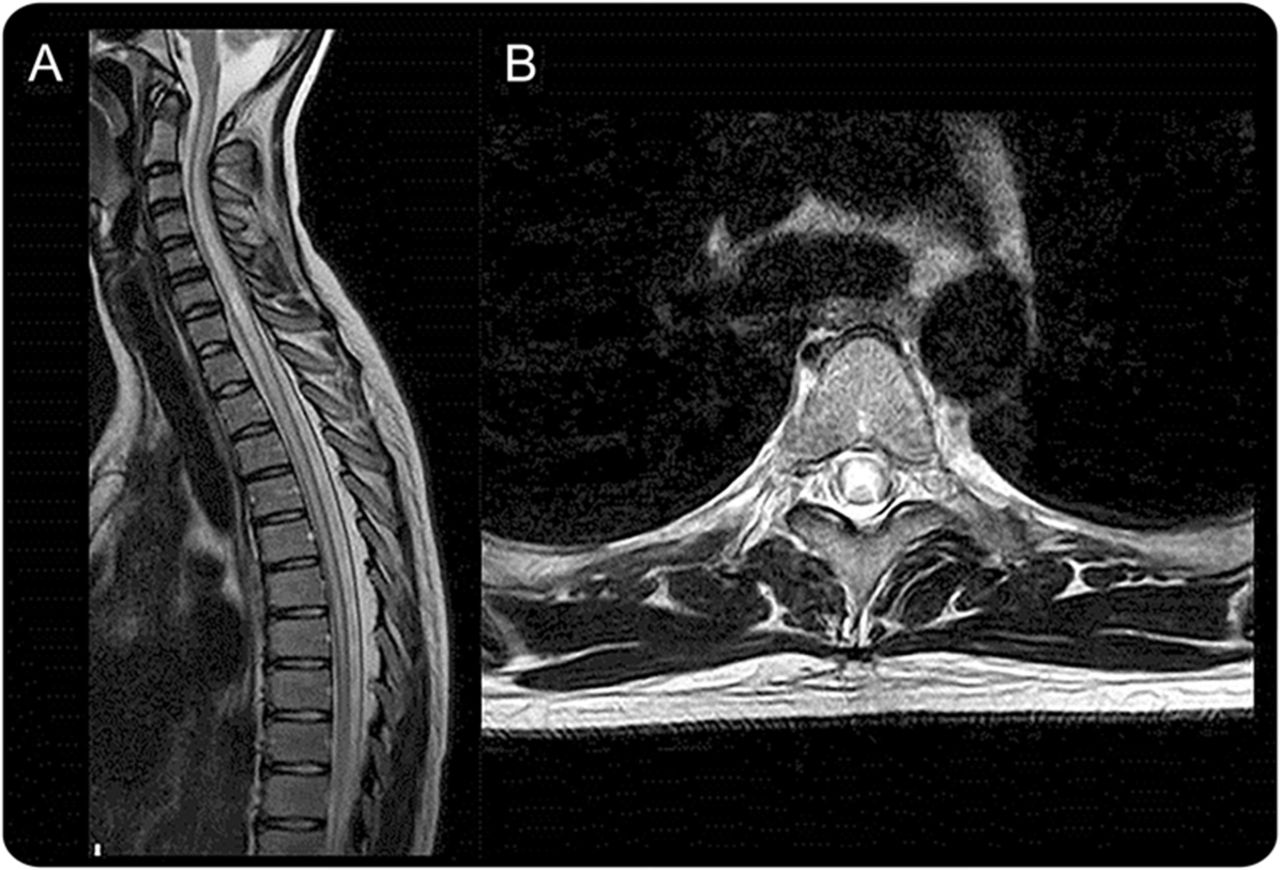

在NMOSD脊髓MRI发现

的炎症过程在脊髓MRI特点是hyperintensity NMOSD t2加权序列和hypointensity在t1序列。这些脊髓MRI异常报告,一般来说,更频繁地出现在颈部和上胸段脊髓胸和腰区域比低23,34,e23优先参与中央灰质。34,35在脊髓,AQP4在灰质和丰富胶质细胞过程毗邻中央管室管膜细胞、脊髓白质的学位。e24

动的最明显的表现是LETM,定义为损伤时间跨度超过3或更多相邻椎段和主要涉及中央灰质在脊髓磁共振成像(图4)。4然而,并不是所有LETM LETM患者NMOSD,几项研究已经观察到显著的人口和临床特征差异anti-AQP4 LETM患者抗体正面与负面。19,36,- - - - - -,38LETM似乎不太特定的动的儿童比成年人。LETM经常被观察到在儿童急性播散性脑脊髓炎39,40也有17%的女士,e25在67%到88%的儿童单相横向脊髓炎。e26, e27因此,重要的是要记住,许多其他比NMOSD鉴别诊断时需要考虑病人与LETM礼物。